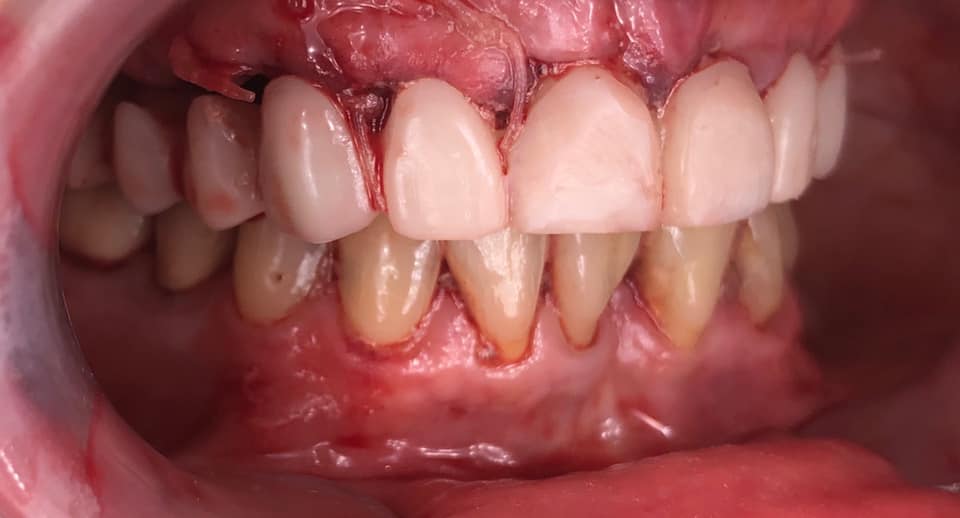

Below is a case of full arch same day temporization using the socket shield , root submergence and pontic shield techniques to preserve the site architecture . Neodent GM implants were placed in a guided fashion and same day temporization was performed using a milled PMMA.

-Immediate load temp upper